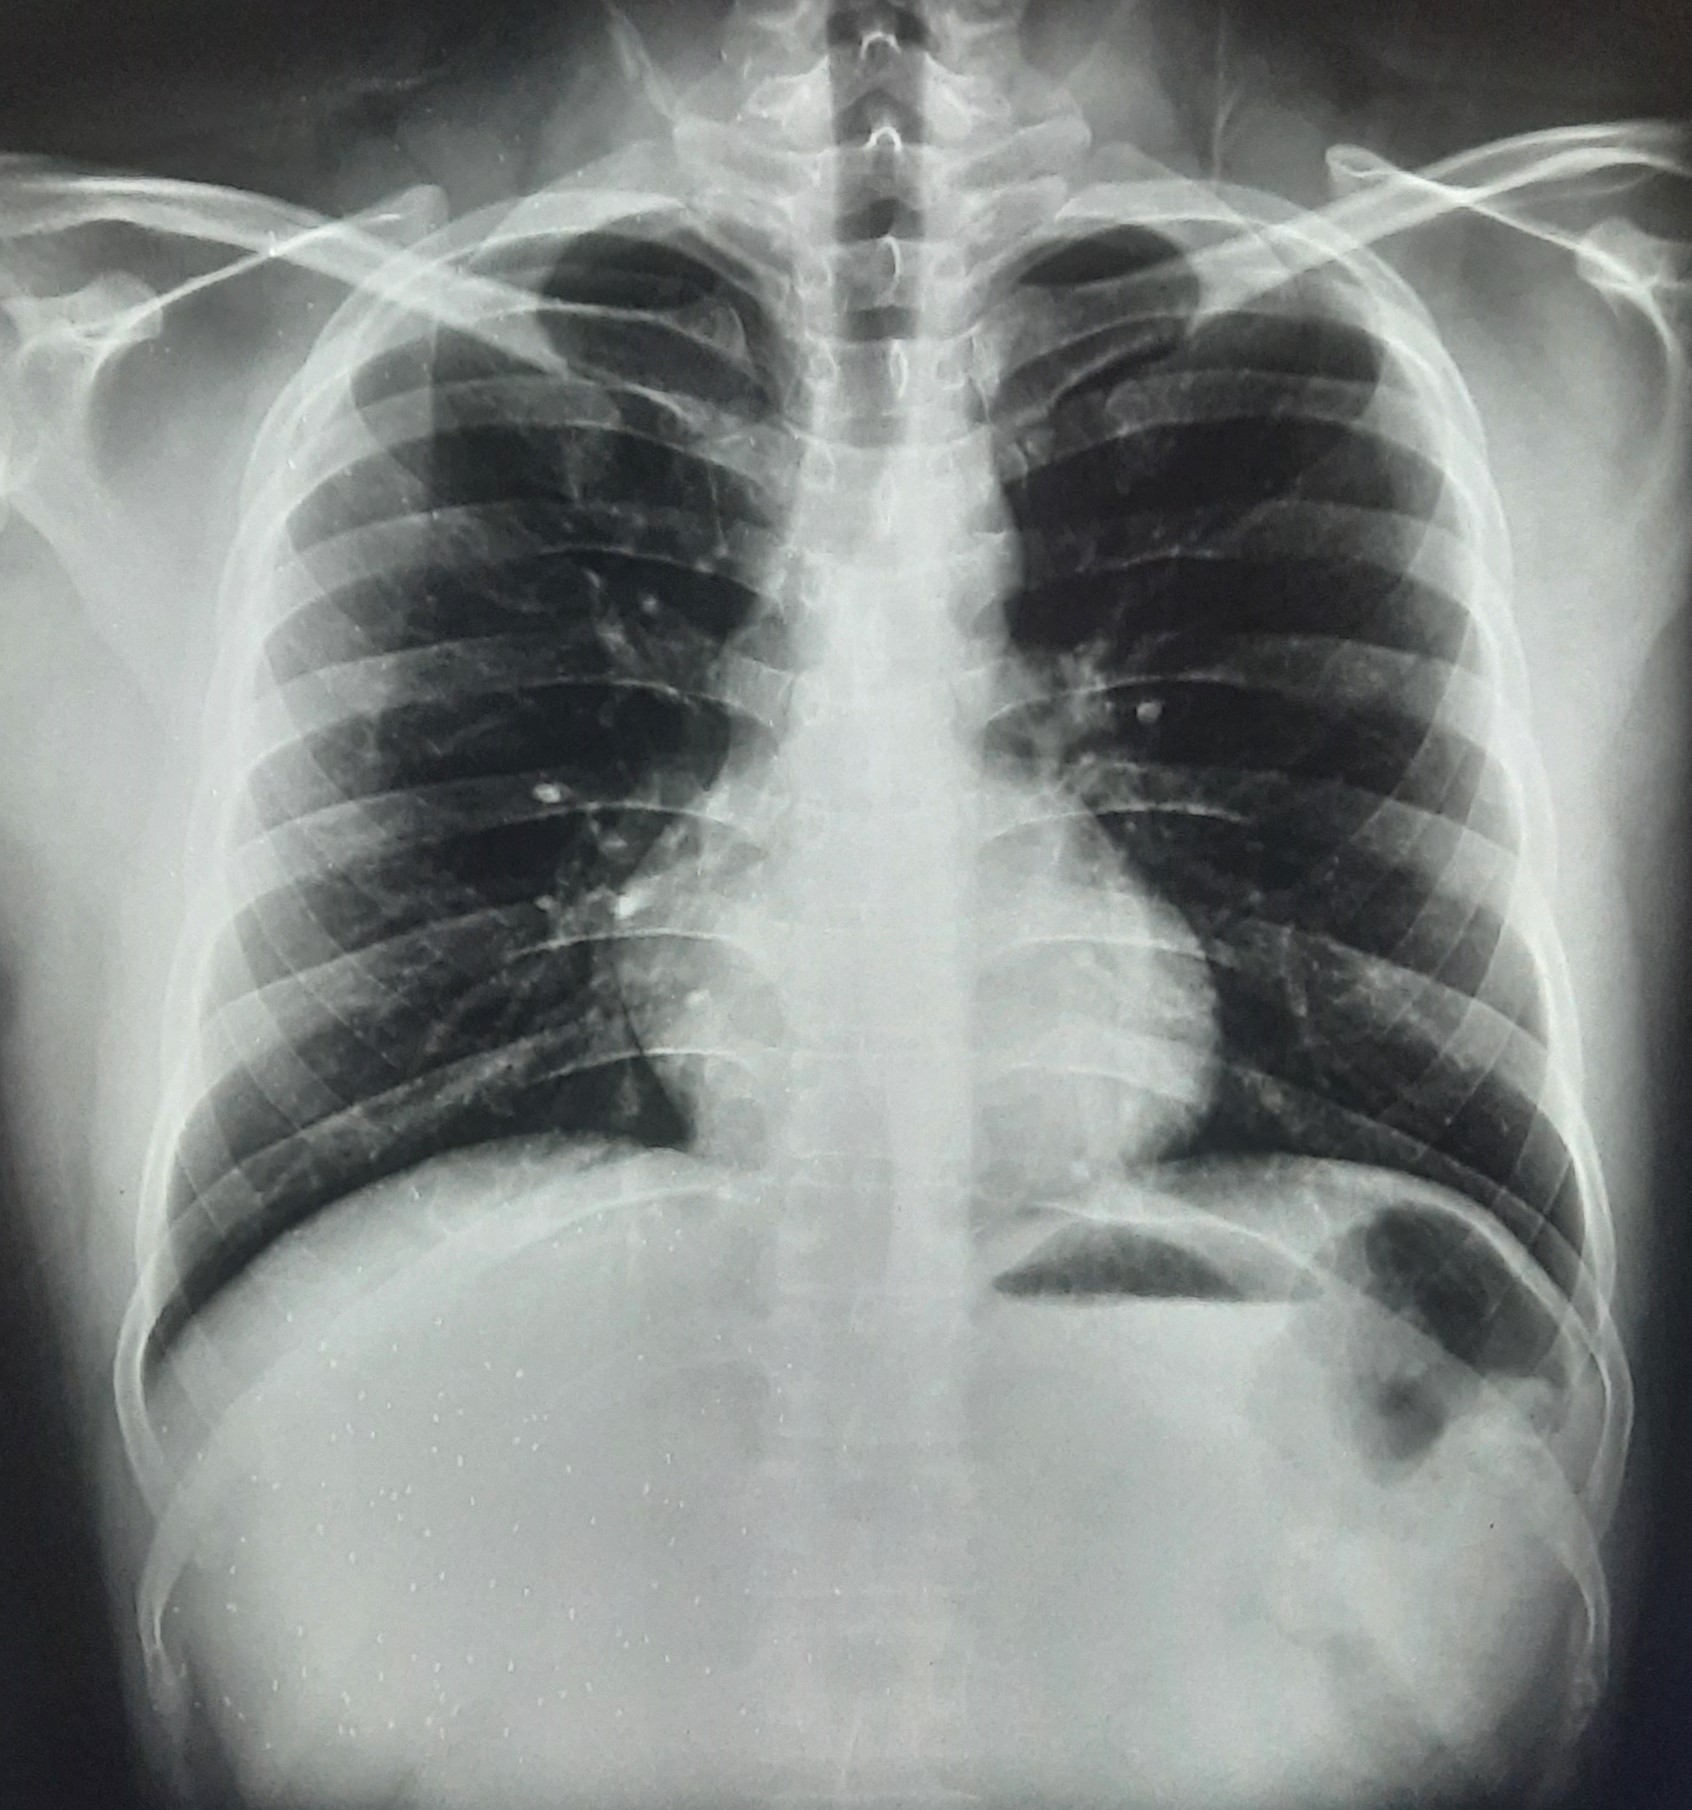

| 283 | IGGMC, Nagpur, Nagpur | P2 | 29-4189 Follow-up of 29-3923 |

Monali Pralhad Milmile | Consent taken on Paper | 46 Yrs. |

Provisional Diag : PTB Follow-up

Final Diag : Pleural Effusion |

TB Case (Confirmed) | Right Sided Upper Zone Fibrotic Lesion, Tracheal Pull Left side, Right sided & Left Sided Pleural Thickening Present, Right sided & Left Sided CP Angle Blunting Present, | Abnormality visible on x-ray |